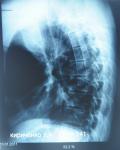

Nikolay Lazarenko Опубликовано 23 мая, 2012 Опубликовано 23 мая, 2012 Pomka.,смотрю зубки у тебя хорошие.Есть ощущение,что прибегал их ремонту Надо бы что-то у себя откопать и выложить.Где-то у меня была флюорография легких в двух проекциях...

Strike Опубликовано 23 мая, 2012 Опубликовано 23 мая, 2012 Надо будет тоже свой пневмоторакс раскопать.

AlexNEW Опубликовано 23 мая, 2012 Опубликовано 23 мая, 2012 пневмоторакс кошмар . Это ж где вы его смогли "подцепить" (ессенциальный, ятрогенный, травматический) ? Если, конечно, не секрет.

Umnik Опубликовано 23 мая, 2012 Опубликовано 23 мая, 2012 (изменено) Совместный рентген нескольких человек из команды Endpoint Изменено 23 мая, 2012 пользователем Umnik

Strike Опубликовано 23 мая, 2012 Опубликовано 23 мая, 2012 (изменено) Спонтанный, но пораскинув мозгами ретроспективно, склоняюсь к травматическому. Изменено 23 мая, 2012 пользователем Strike